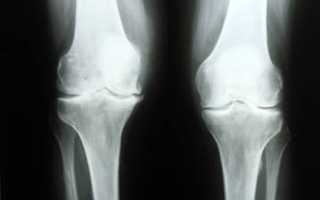

рентген колена

Обзорный рентген

Такой вид обследования коленного сустава позволяет визуализировать отдельные части сустава, в зависимости от того, в каких проекциях проводились снимки. Благодаря такой диагностике можно увидеть различные изменения, произошедшие с костными тканями.

Назначают обзорный рентген после получения травм, при подозрении на перелом, вывих, растяжение. Поможет такой рентген диагностировать и дистрофические изменения, сопровождающиеся сужением суставной щели, наличием неровностей на костях, остеофитов и других наростов.

Можно выявить и патологии, связанные с изменением структуры костных тканей. Так диагностируется остеопороз или остеоартроз. Отображает рентген и наличие врожденных изменений костей в виде несоразмерности окончаний костей, наростов и выпуклостей. Незаменимо рентгенологическое исследование для диагностики опухолей, появившихся как на костных, так и в мягких тканях.